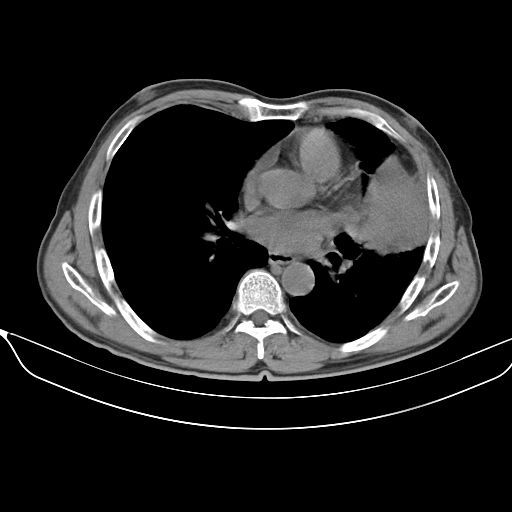

以下是引用shuiyuan在2010-3-1 10:45:00的发言:[br]考虑左肺上叶中心型肺癌伴阻塞型炎症,邻近胸膜受侵。

以下是引用心路寻觅在2010-3-1 10:23:00的发言:[br]1、考虑左肺上叶周围型肺癌[br]2、右上肺陈旧性病灶。[br][br][本贴已被 心路寻觅 于 2010-3-1 10:40:18 修改过]